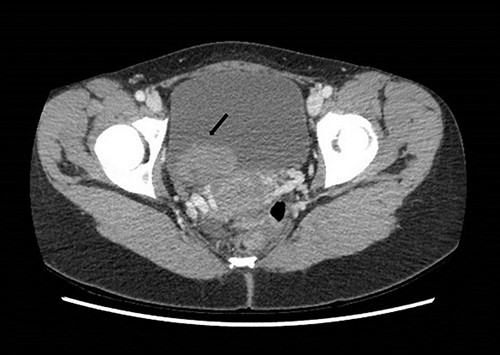

The patient received a bladder washout and continued on continuous bladder irrigation. She was afebrile and normotensive. Laboratory findings showed raised creatinine at 140 mmol/L, Hb was 13 gm/dL with subsequent drop to 9 gm/dL during the admission. Urine culture didn’t show signs of infection. Computed Tomography (CT) abdomen and pelvis with contrast demonstrated a solid mass in the bladder and a hypodense filling defect extending from the left renal pelvis to the proximal ureter with hydronephrosis (Figs 1 and 2).

Computed tomography on presentation showing a bladder mass (arrow).